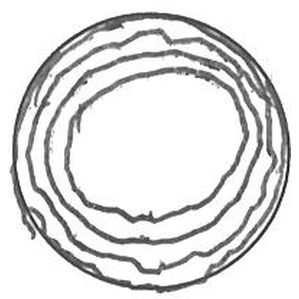

TASK_04: Trace Circle

Healthy Control

Alzheimer's

Real handwriting samples across 6 different tasks showing motor control and cognitive differences between healthy controls and Alzheimer's patients